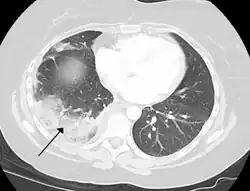

Infarction of the lung due to a pulmonary embolism

Because of the dual blood supply to the lungs from both the bronchial and the pulmonary circulation, this tissue is more resistant to infarction. An occlusion of the bronchial circulation does not cause infarction, but it can still occur in pulmonary embolism when the pulmonary circulation is blocked and the bronchial circulation cannot fully compensate for it.[2]